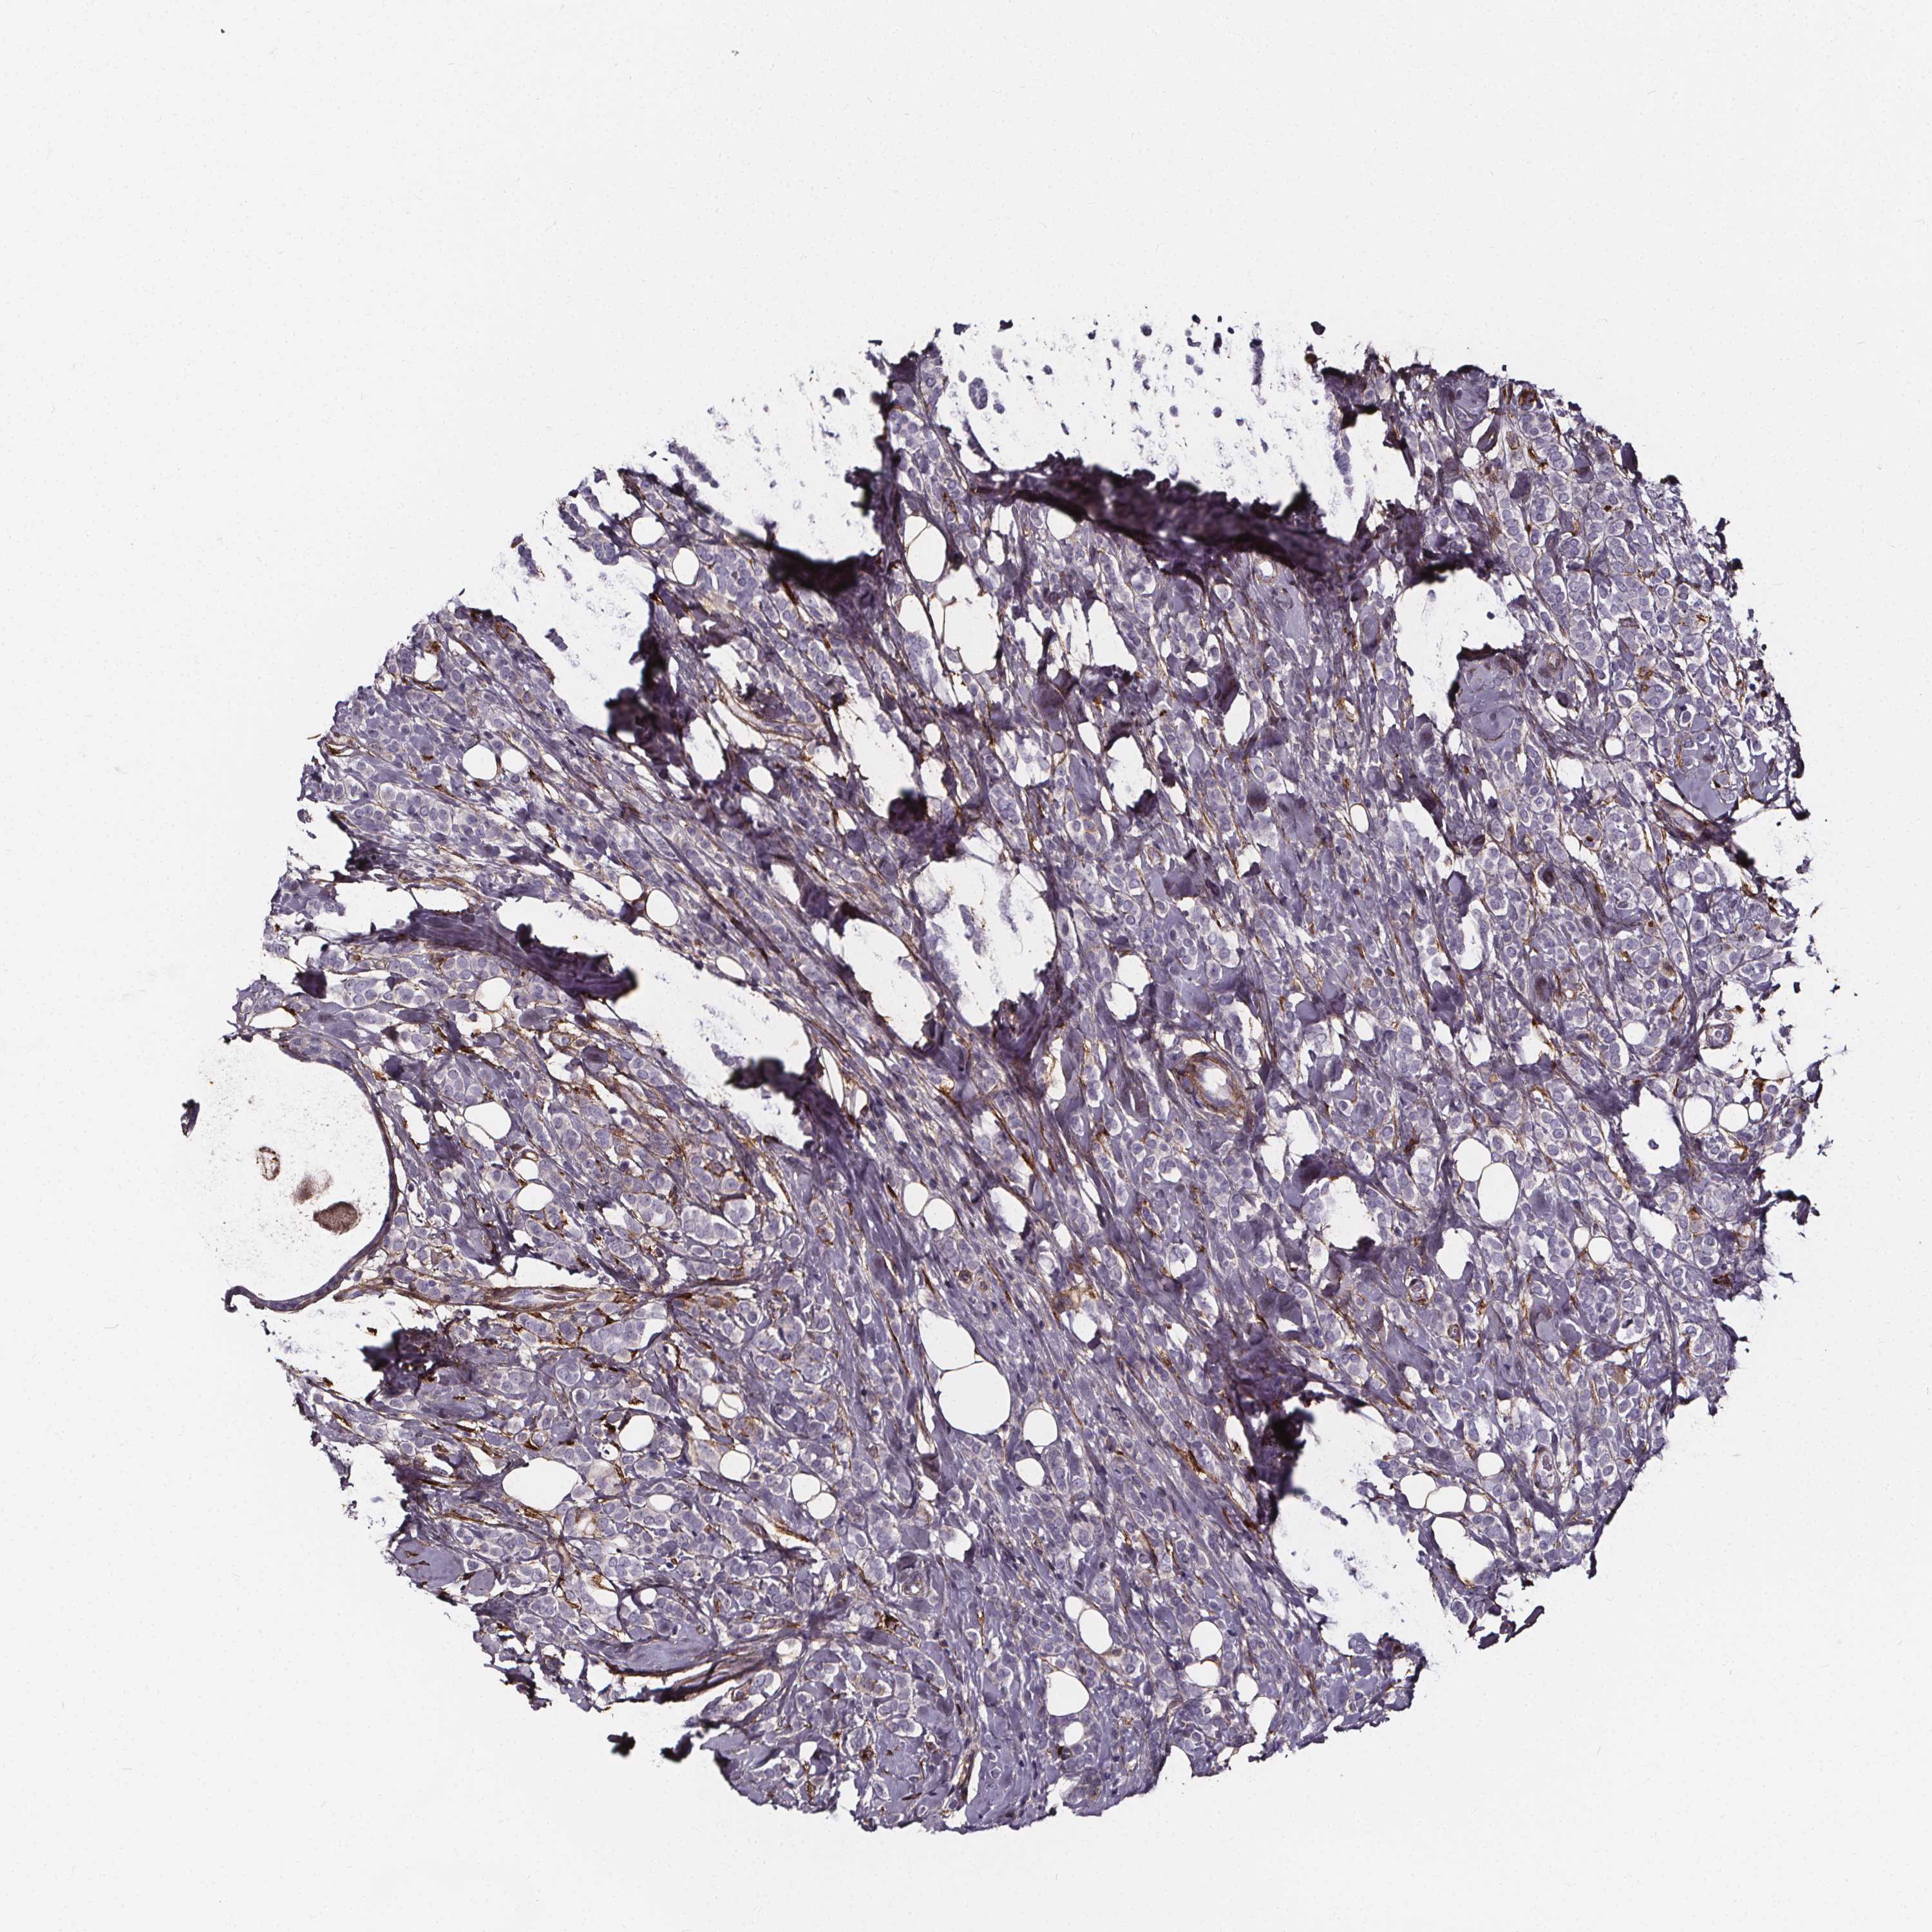

BRCA TCGA BRCA VALIDATION PROTEIN EXPRESSION